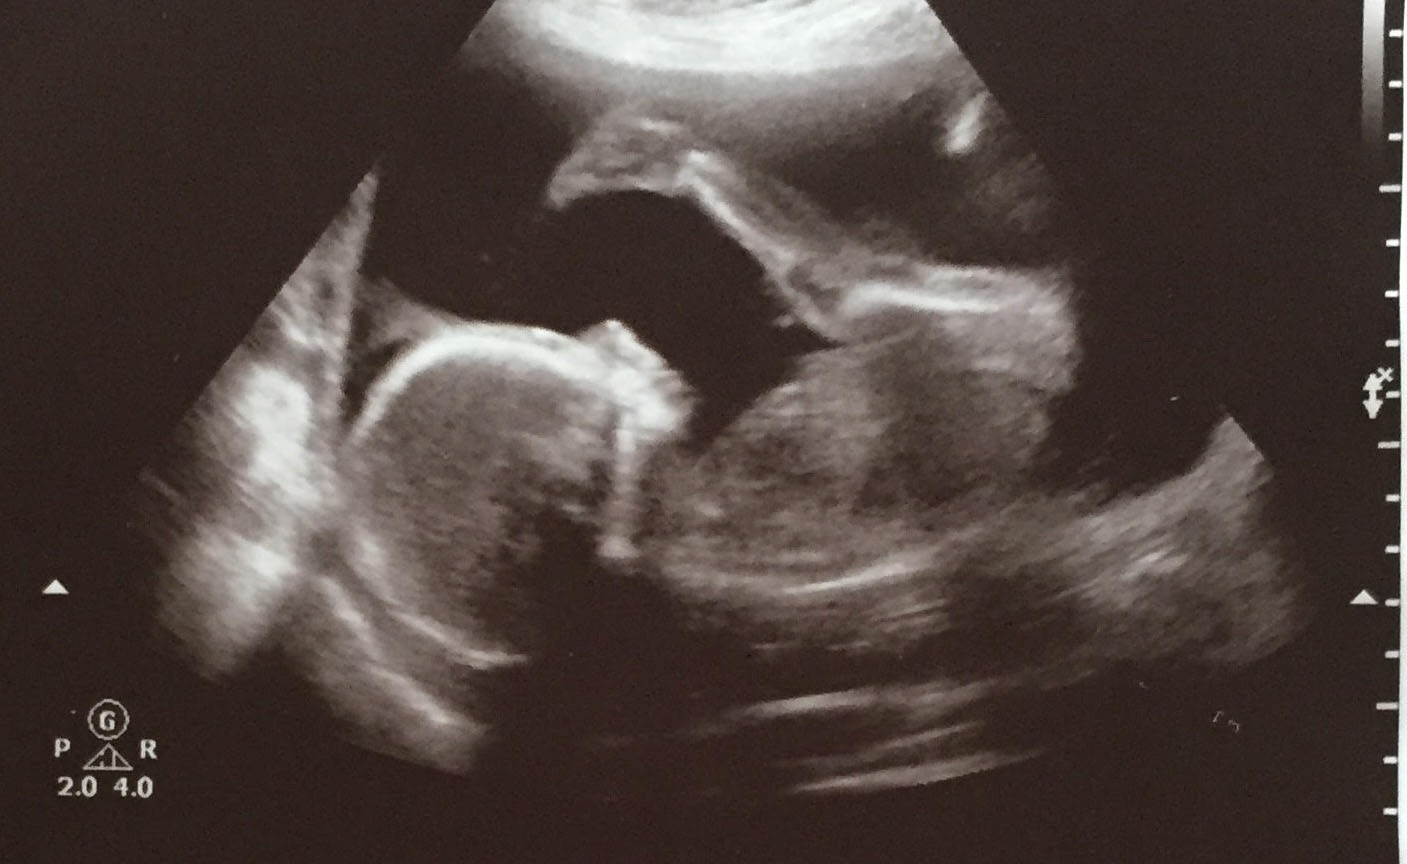

We announced to the world on Christmas Day, 2019, that we are expecting a second child in May 2020. Its due date is May 17th,… Read More »Print Nugget 2: Al A. Poopy’s Revenge!